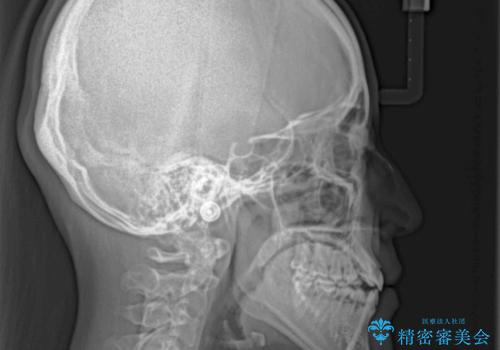

- 前歯の開咬と、上顎前歯の八重歯やデコボコを気にして来院された患者様です。

上顎歯列が狭窄していたため、急速拡大装置により上顎骨を側方に拡大し、その後ワイヤー装置にて矯正治療を行うこととしました。